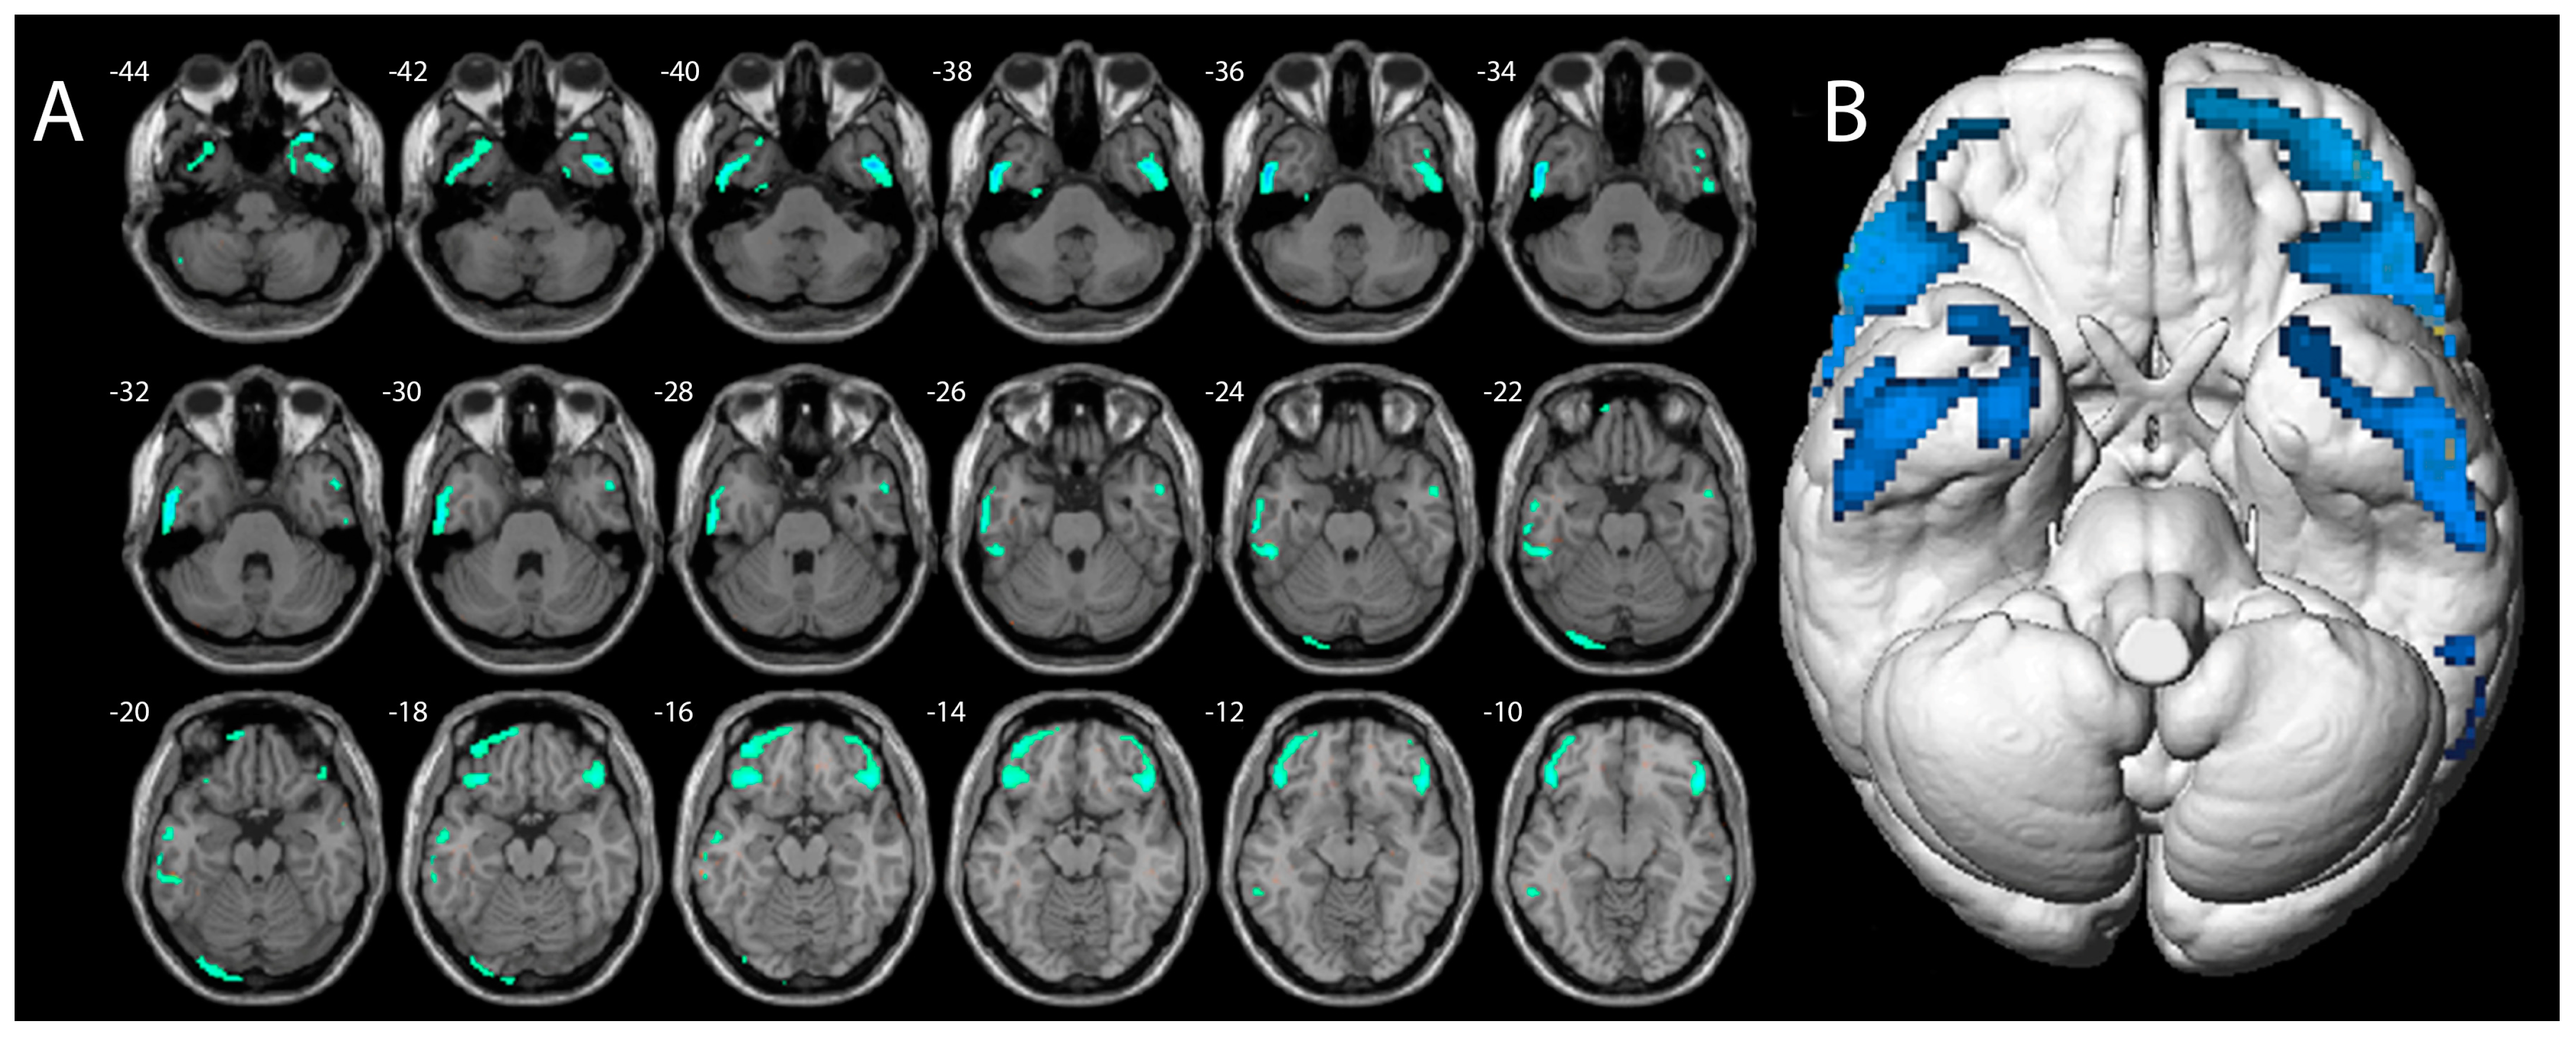

The voxel-wise analysis, using p values of <0.001, showed lower 18F-FDG-PET uptake in the bilateral inferior frontal cortex and bilateral temporal inferior cortex compared to healthy controls (Figure 3).

Figure 3.

Axial magnetic resonance slices (A) and brain surface rendering (B) show the results of SPM analysis. The color-coded regions indicate the locations where the patients’ voxel values are significantly hypometabolic compared with the healthy control group (p < 0.001).

Specifically, clusters of major hypometabolic voxels were found in the right inferior frontal gyrus, with a peak at 58/30/4 mm (1036 voxels, T-Score 7.9), and in the inferior and middle temporal gyrus, with a peak at 46/2/−40 mm (522 voxels, T-Score 7.8). Conversely, by setting the voxel-wise analysis to reveal regions of increased 18F-FDG uptake, no voxels of significant hypermetabolism were found in comparison to healthy subjects (p values > 0.001).